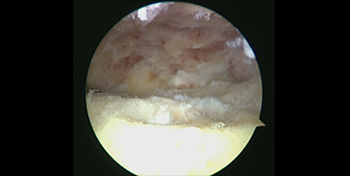

- Day 0 – Images obtained during surgery – Note the scar tissue and bone spur at the front of the ankle.